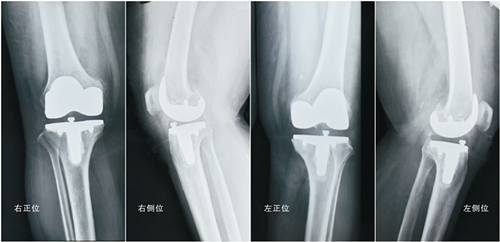

˫��ϥ�ؽ��û�����ͼƬ

����XƬʾ��˫��ϥ�ؽڼ���λ�����ã�ϥ�ڷ����εõ�����

������������·���Ҷ�������롣����������Ůʿ���������ˣ�������˵���������3�죬�Ҿͷ����´������ˣ������Ѿ����Զ���վ�����ȹ���ʱ��ȫ�ָ��ˣ��͵���תת�������������õ�������������